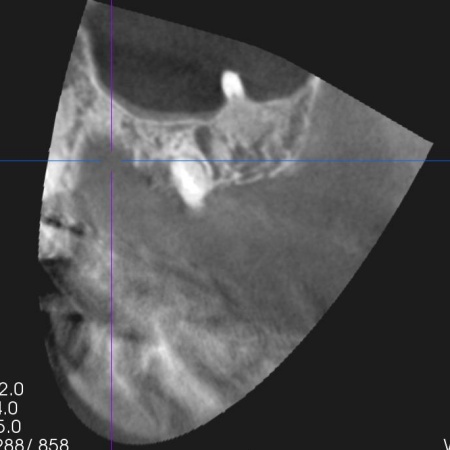

| 診断 | 拝見したところ、左上奥歯(第2小臼歯)1本が折れ、歯根だけの状態になっていました。 レントゲン撮影をして詳しく検査した結果、治療して温存することは困難な状態だったため、残っている歯根を抜き、欠損部分を補う治療が必要だと判断しました。 患者様は、人工歯根であるインプラントによる治療を希望されていましたが、レントゲン撮影の結果では、インプラントを入れるために必要な骨の量が足りていません。 以上のことから、まずは慎重に治療方法を検討する必要があると診断しました。 |

| 行ったご提案・治療内容 | 患者様には、折れた左上奥歯は温存ができず、歯根を抜く必要があることをお伝えしました。 そのうえで、希望されているインプラント治療を行うために必要な点を説明しています。 ・インプラント治療に必要な骨の量を確保するための「骨補填」を行う こちらに同意いただき、3ヶ月後からインプラント治療を始めることになりました。 まず、左上奥歯を抜きます。 3ヶ月後、顎の骨の状態が良好であることを確認し、インプラントを埋入する手術を実施しました。 |

治療中